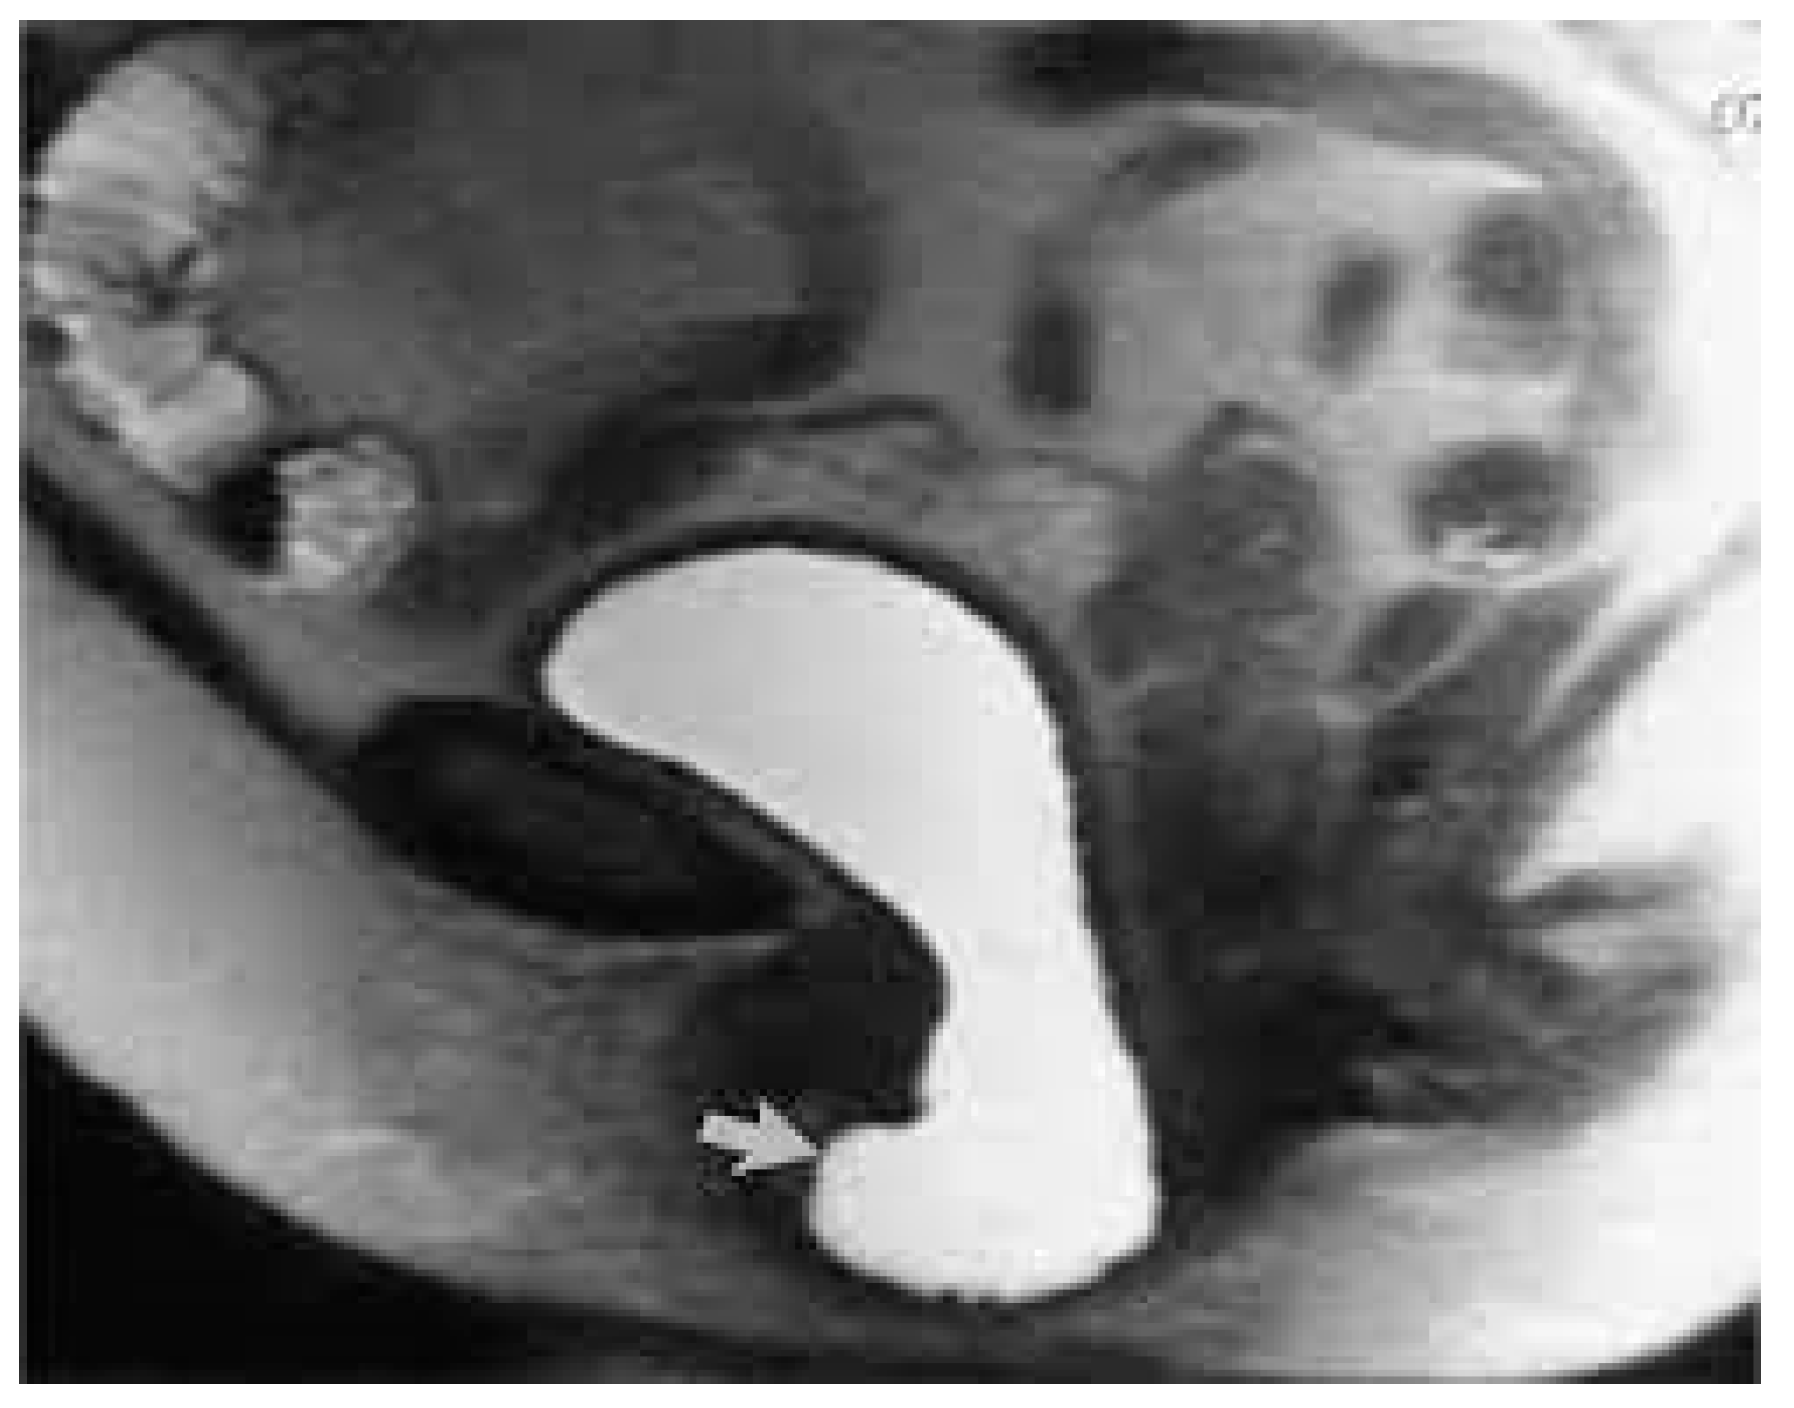

Figure 2.

MRI—T2 weighted image of high-grade anterior compartment prolapse.

Pelvic organ prolapse (POP) is defined as the descent of one or more of the anterior and posterior vaginal walls, the uterus (cervix), or the apex of the vagina outside their usual anatomical location [1]. POP occurs in about 40% of females worldwide [2]. A cystocele is a specific type of POP known as an anterior vaginal wall prolapse [3]. This pelvic floor defect occurs when the supportive tissues around the bladder and vaginal wall, which serve to support the vaginal wall and hold the bladder in its normal anatomical position, weaken and stretch, allowing the bladder and vaginal wall to fall into the vaginal canal as shown in Figure 1, Figure 2, Figure 3 and Figure 4, which illustrate images and the dissection of a high-grade cystocele after retropubic sling placement. Often, this pelvic floor defect of the anterior compartment involves inadequate urethral closure. This impairment in urethral closure and associated anatomical changes in urethral function may lead to stress urinary incontinence [4]. Concomitant pelvic organ prolapse, and stress urinary incontinence represent a significant diagnostic, clinical, and surgical dilemma for pelvic-floor surgeons.

It is well-known that POP and SUI often coexist, particularly in advanced stages of POP. The prevalence of these conditions occurring together varies depending on the severity of the prolapse and other risk factors, such as obesity, pelvic floor tissue integrity, and having undergone prior pelvic floor surgical interventions [16]. When using the Pelvic Organ Prolapse Quantification system (POP-Q), an objective, site-specific system for describing, quantifying, and staging pelvic support in women [17], it was demonstrated that over 50% of patients with stage IV (Figure 1 and Figure 2) POP-Q (leading edge ≥ +(TVL-2) cm) (Figure 5) pelvic organ prolapse also had SUI as assessed via urodynamic testing [6]. Of the patients diagnosed with SUI, 40% were asymptomatic [18].